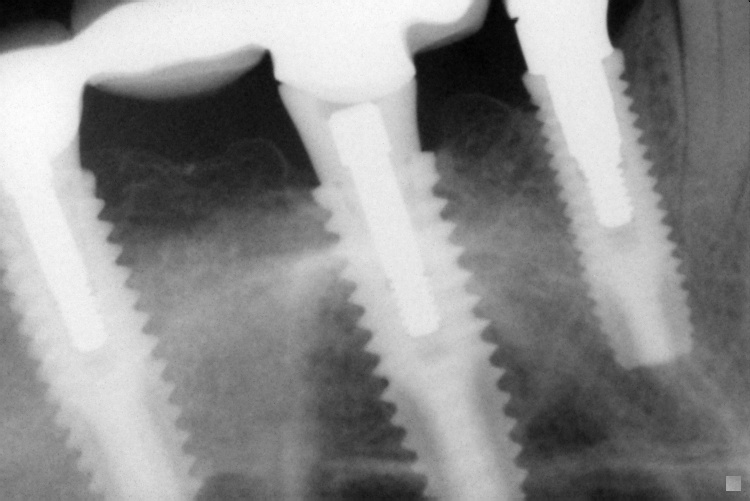

Name Last modified Size Description Parent Directory - IO000001.jpg 2020-07-28 13:36 71K IO000002.jpg 2020-07-28 13:36 88K IO000003.jpg 2020-07-28 13:36 82K IO000004.jpg 2020-07-28 13:36 85K